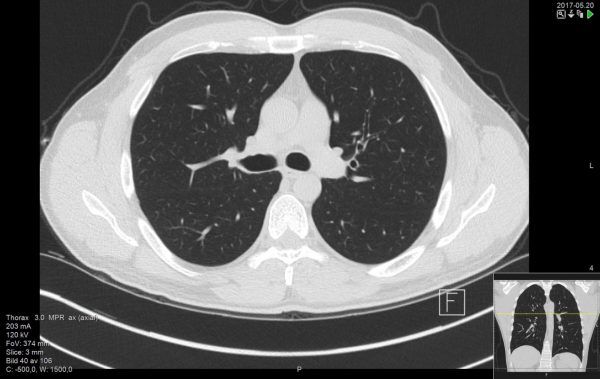

Αναφερόμενη στη διάγνωση της νόσου, η κ. Κατερίνα Μαρκοπούλου, Πνευμονολόγος, Διευθύντρια ΕΣΥ, υπεύθυνη του Εξωτερικού Ιατρείου Διαμέσων Πνευμονοπαθειών και Σαρκοείδωσης στο νοσοκομείο «Γ. Παπανικολάου» επεσήμανε πως αν τεθεί η υποψία για Ιδιοπαθή Πνευμονική Ίνωση από κάποια χαρακτηριστικά ακροαστικά (ήχοι velcro) ή ευρήματα στην ακτινογραφία θώρακα, η επιβεβαίωση έρχεται με την αξονική τομογραφία θώρακα υψηλής ευκρίνειας, η οποία προσφέρει πολλές πληροφορίες σχετικά με το είδος, τα χαρακτηριστικά και την έκταση της νόσου.

Αν τα ακτινολογικά ευρήματα είναι τυπικά, η πάθηση μπορεί να χαρακτηριστεί με βεβαιότητα.

Διαφορετικά χρειάζεται ιστολογικός έλεγχος με κάποια βιοψία πνεύμονα ή εξέταση των κυττάρων που βρίσκονται στις κυψελίδες. Τα κύτταρα αυτά μπορούν να εξετασθούν με βρογχοσκόπηση, αντλώντας κύτταρα από το περιεχόμενο των κυψελίδων, με διαβρογχική βιοψία ή κρυοβιοψία πνεύμονα, ή σπανιότερα με χειρουργική λήψη βιοψίας πνεύμονα.

Η μαγνητική τομογραφία δεν έχει θέση στη διερεύνηση αυτής της πάθησης.